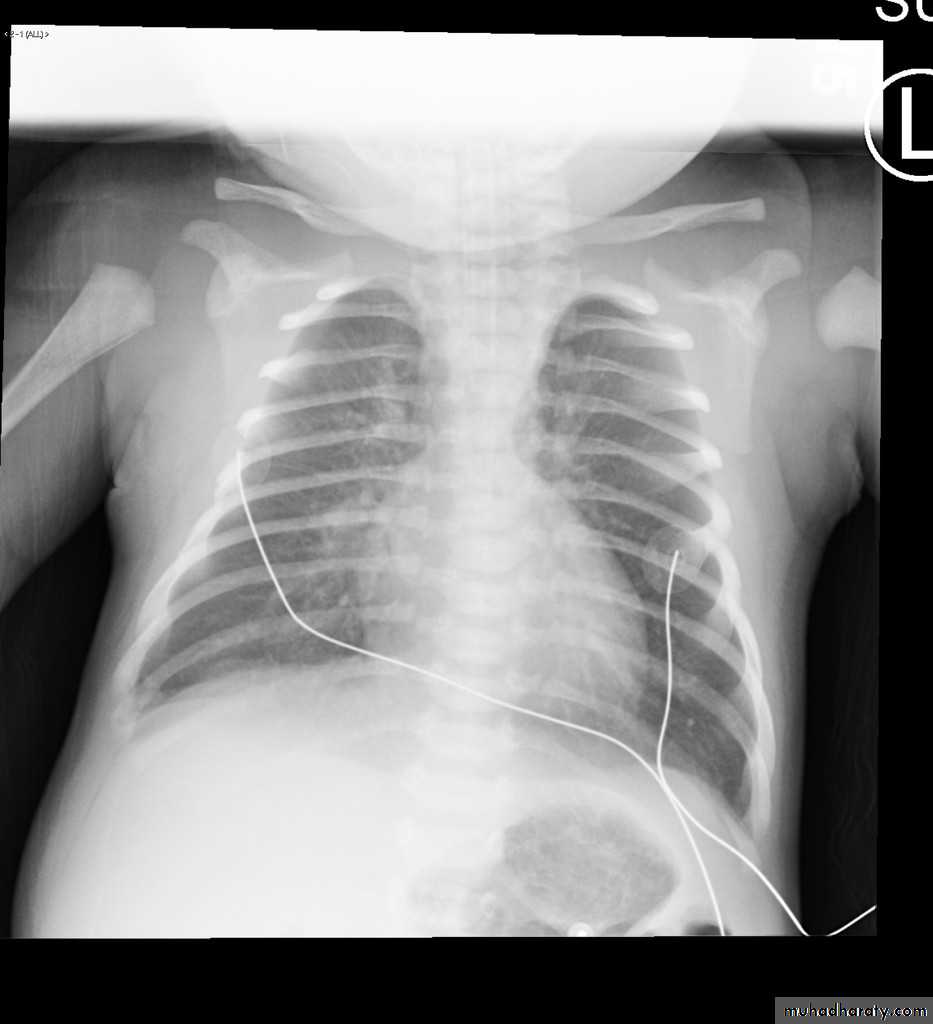

23.normal neonatal chest XR ( normal thymus gland )

24. normal chest XR of the infant( normal thymus gland)